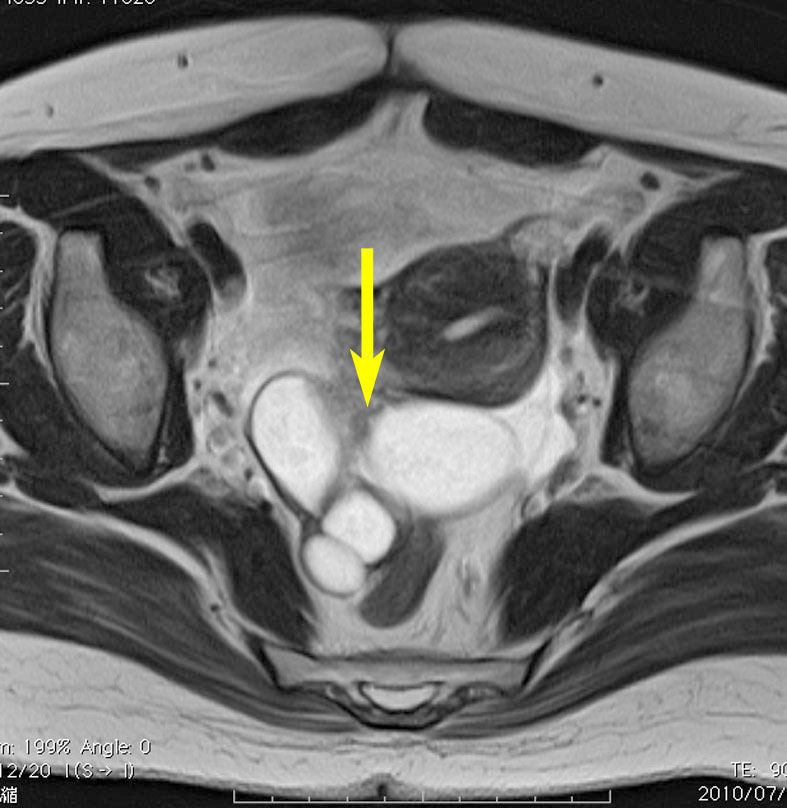

FSH産生腫瘍による卵巣過剰刺激症候群です。30代女性,数年間の月経不順の後で,両側の卵巣の多房性腫大 follicular cysts をきたしました。一度のう胞摘出を受けたのですが,のう胞性腫大が再燃して,FSHの軽度の上昇が疑われました。下垂体腺腫を全摘出したら卵巣のう胞は縮小して治りました。病理でFSHがびまん性に陽性なFSH産生腺腫の診断です。